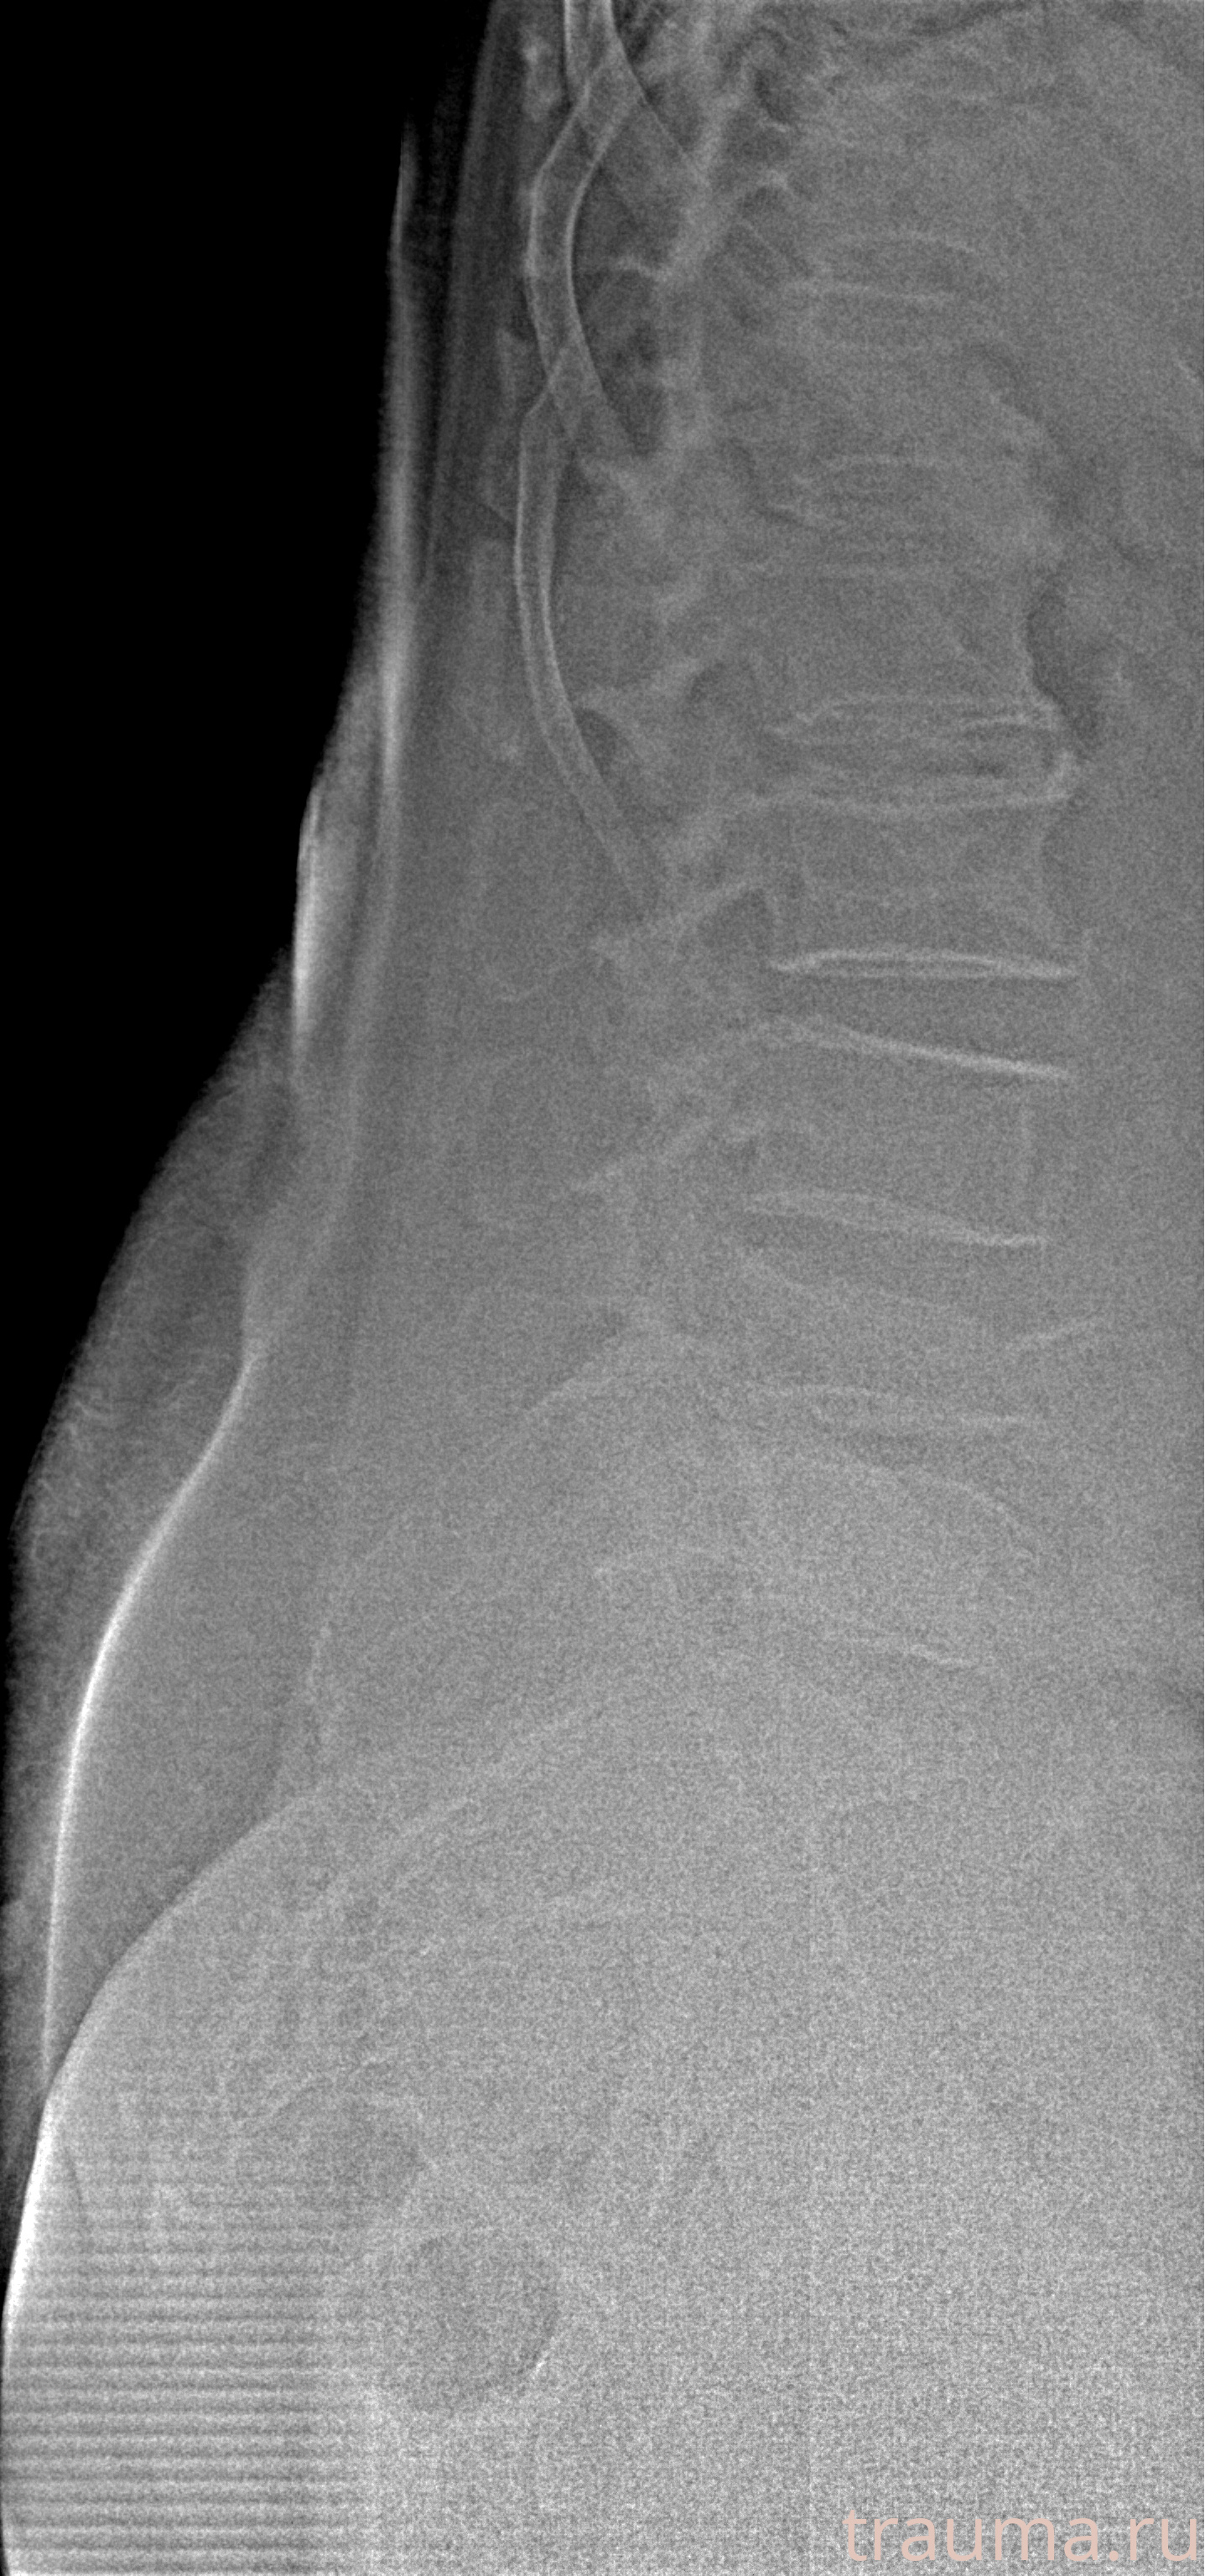

Рентген на дому: по вашему адресу приезжает врач-рентгенолог, травматолог-ортопед с мобильным рентгеновским аппаратом, проводит диагностику травмы или заболевания, делает необходимые рентгенограммы, дает рекомендации по дальнейшему лечению. Получить качественные снимки в домашних условиях возможно благодаря уникальной методике, разработанной МосРентген Центром для института  Склифосовского